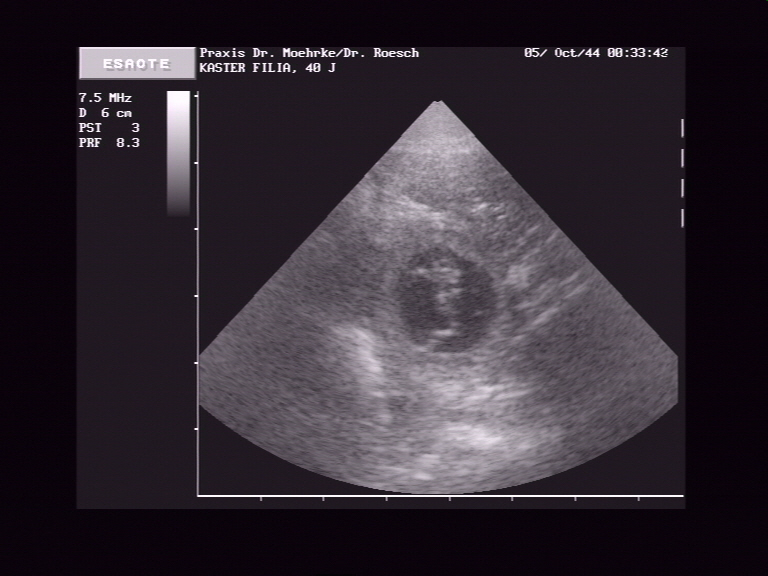

Ultraschall am 16.04.07

*   *

*Datum auf der Aufnahme stimmt leider nicht